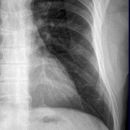

Thorax seitlich

Darstellung der Sagittalebene des Thorax und der Brustorgane, anliegende Seite richtet sich nach dem Befund, ohne spezielle Angabe wird generell links anliegend geröntgt. Atemphase: maximale Inspiration.

Wirbelsäule rein seitlich, Sternum seitlich getroffen, komplette Darstellung der Lunge von Lungenspitze bis einschließlich Rippen-Zwerchfell-Winkel. Die Mediastinalstrukturen und retrocardialen Gefäßabschnitte sind gut differenzierbar und der Herzhinterrand scharf abgrenzbar.